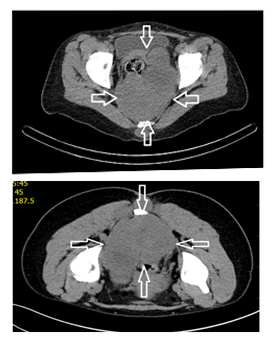

1. Static Computer Tomography (CT) scans of the chest, abdomen and small pelvis with CT biopsy sampling of the sacral expansion (Figure 1). In addition to the sacral tumorous expansion the CT scan captured suspected multiple diffuse metastatic diseases of the lungs and both pulmonary hilum (Figure 2). Other organs or the skeleton were not affected.

Figure 1 Computer tomography (CT) scan of the small pelvis - sacral expansion.